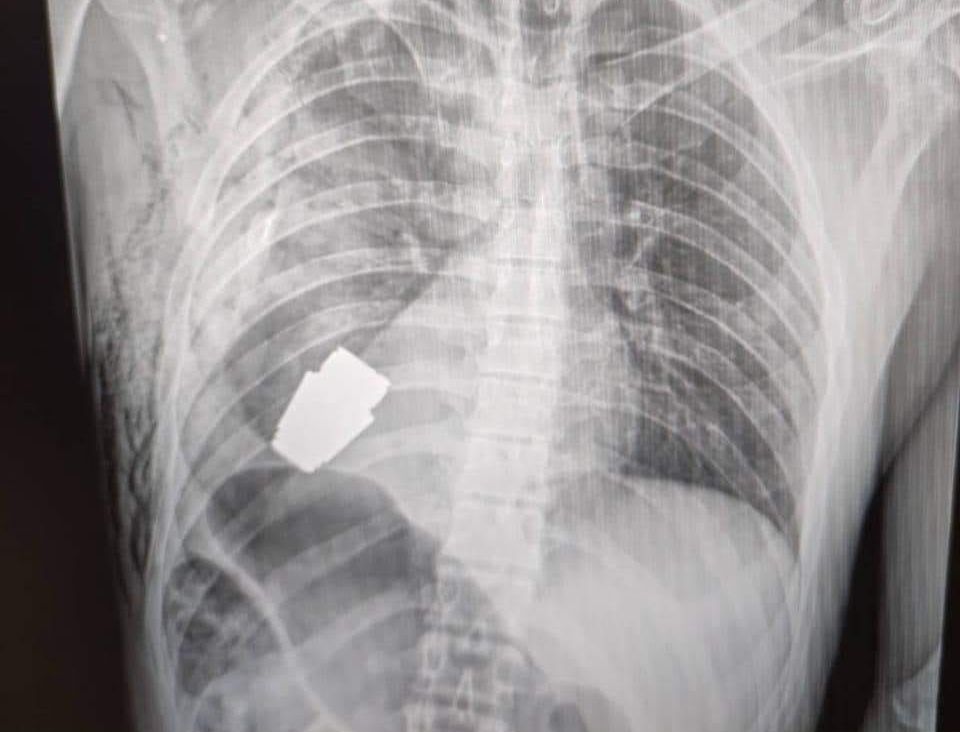

▲烏克蘭一名士兵心臟附近卡了一顆VOG榴彈 。(圖/翻攝自臉書,下同)

綜合衛報、天空新聞報導,這名士兵是在烏東前線巴赫姆特(Bakhmut)作戰時受傷,依據X光影像,可見一顆尚未爆炸的VOG榴彈就卡在他的胸腔,位置就在心臟下方。